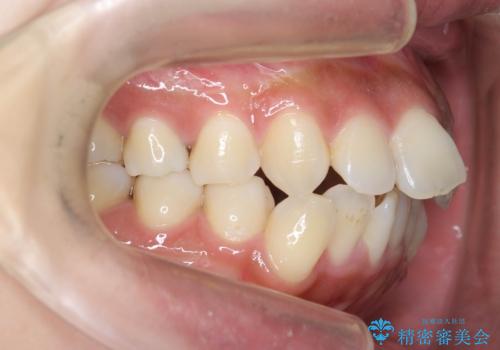

ガタつきと口元の改善 抜歯を伴うワイヤー矯正

- 唇の閉じづらさと、前歯のがたつきの改善を希望され来院されました。

抜歯を行わなくてもなんとか並べられる歯並びですが、唇の閉じづらさをしっかりと改善するため抜歯を伴うマルチブラケット矯正を行うこととしました。

前歯をしっかりと後方に引いたことで、唇は閉じやすくなり、仕上がりに満足いただくことができました。